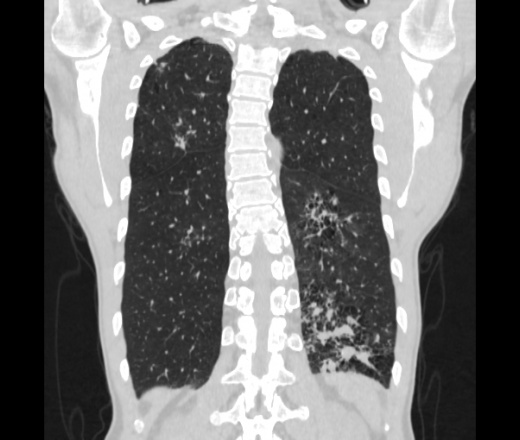

Мужчина пенсионного возраста. Цель назначения КТ ислючение зла в левом легком. Вижу тракционные бронхоэктазы с рубцовой эмфиземой по периферии, скорее всего БЭБ в стадии обострения. Дивертикулы трахеи. Выложил из за того что есть доля сомнения в отношении исключения зно3, немного смущают линии похожие на Керли.

Единственно, не сказал бы, что это тракционные бронхоэктазы, ну, и про линии Керли не вполне понял.

Ну да. Выразился не правильно. На фоне легочного рисунка усиленного линии похожие на септальные, не знаю как называются, при интерстиц.отеке похожие

На мой взгляд, это не главное, указал бы в описании - локально утолщен междольковый интерстиций, и всё